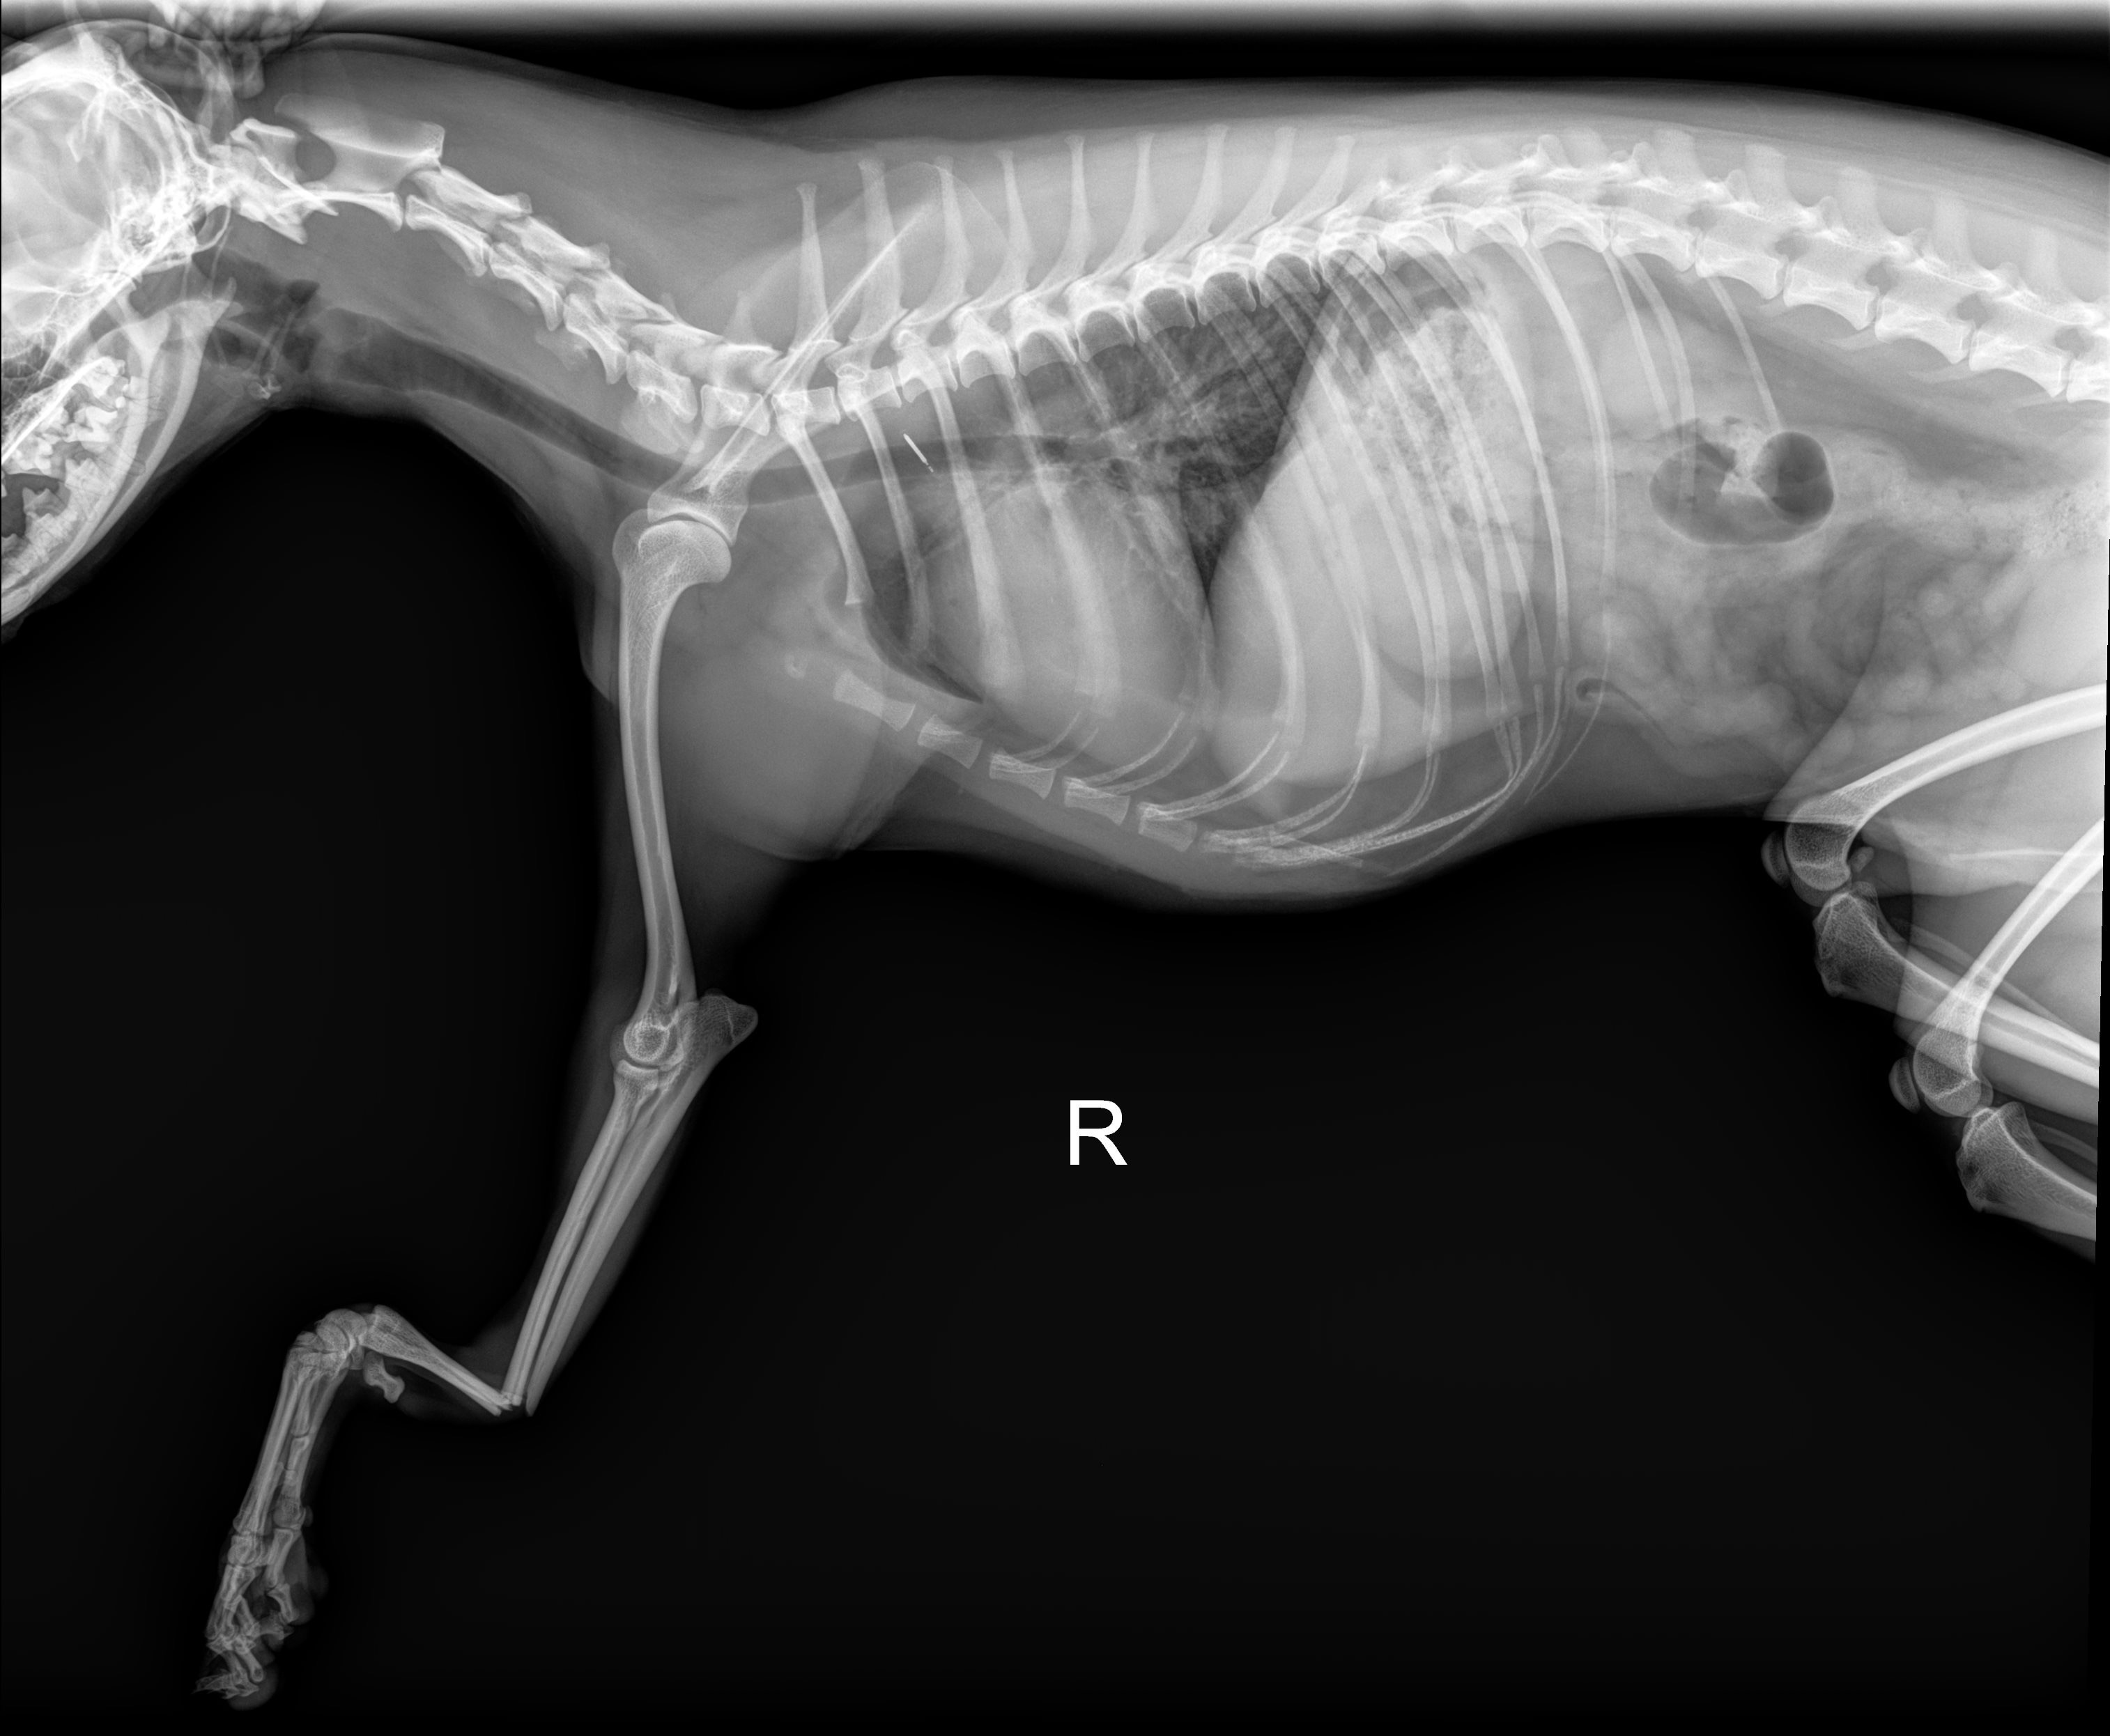

Hi everyone - meet Sushi. He is our 1-year-old, tripod Chihuahua. On December 30th, he slipped and took a tumble while hopping down from the couch and landed terribly wrong on his one front leg. Unfortunately, he broke both his radius and ulna, resulting in needing immediate surgery. He has been a very brave boy while getting it set and splinted in his cast.